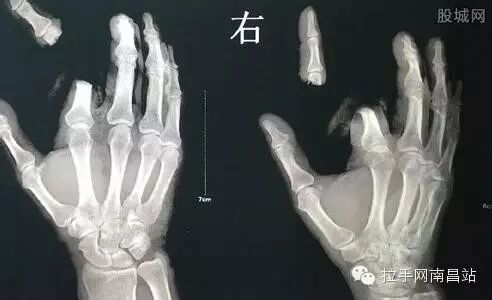

虽然隐翅虫会引发皮肤炎症,但网上有流传隐翅虫含有剧毒致死的谣言,还有人因为轻信隐翅虫剧毒谣言,挥刀斩断食指。

4月27日湖南省常德市澧县,一男子用手指将一只隐翅虫碰碎,不慎沾上少许毒液。他想到自己看到的有关隐翅虫毒液可轻易致人死亡的文章,觉得自己也出现了类似的症状。情急之下,该男子竟拿起菜刀将自己右食指砍下。

随即,家人将其送到常德常武医院手足显微外科救治。该院院长孙培厚告诉记者:“隐翅虫皮炎,是湖南地区的常见皮肤病例。虽然会引发皮肤红肿溃烂,但并不会导致人体死亡。”